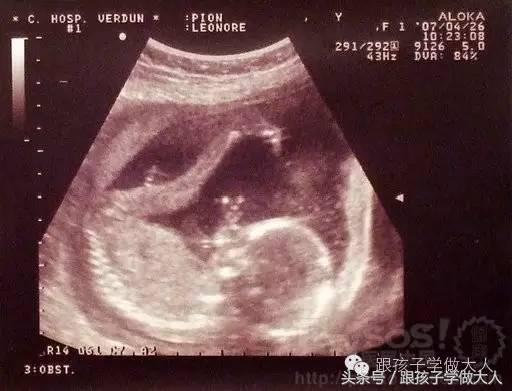

孕期B超检查的目的是为了监测胎宝宝的生长发育,降低畸形儿和有缺陷儿的出生率。但也有不少准妈妈对做B超心存疑虑。

从原理上分析,B超是超声传导,不存在电离辐射和电磁辐射,对人体组织没有什么伤害。它对胎宝宝的影响主要表现在热效应上,很早即有研究表明,低频率、短时间的超声检查对胎宝宝无影响。

但不建议持续长时间做超声检查。孕3个月内少做且尽量缩短照射时间。至于次数上一般无须严格控制。出于安全考虑,一般建议准妈妈孕期做B超在4次左右(12周,24周,32周,37周)。